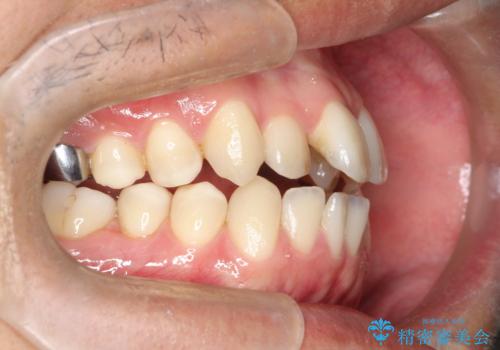

【MSE+インビザライン】前歯のガタガタ

- 前歯の凸凹を主訴に来院されました。

上の歯のアーチが狭窄していたため、骨の幅を広くするためにMSE(急速拡大装置)を使用してからインビザライン にて治療を行いました。

MSE(急速拡大装置)を用いたことで、短期間で奥歯の噛み合わせもしっかりと治すことができました。